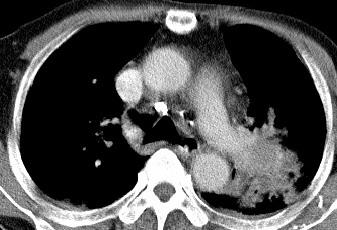

以下是引用xianxianzhongyi在2008-4-20 14:44:00的发言:[br]本人愚见:次病例短短两月的时间,呈现如此大面积实变,病变增长过于迅速,此其一。其二,病变在动脉早期既有明显强化。其三,左上叶后段及下叶背段多叶受累。其四,肺门及纵隔内未见明显肿大的淋巴结。估计层面较厚段支气管显示不清。 诊断:炎性实变可能性大。

以下是引用光影相伴在2008-4-20 14:39:00的发言:[br]支持:1)左侧中央型肺癌伴左肺上叶阻塞性肺炎。、[br] 2)双侧少量胸腔积液。